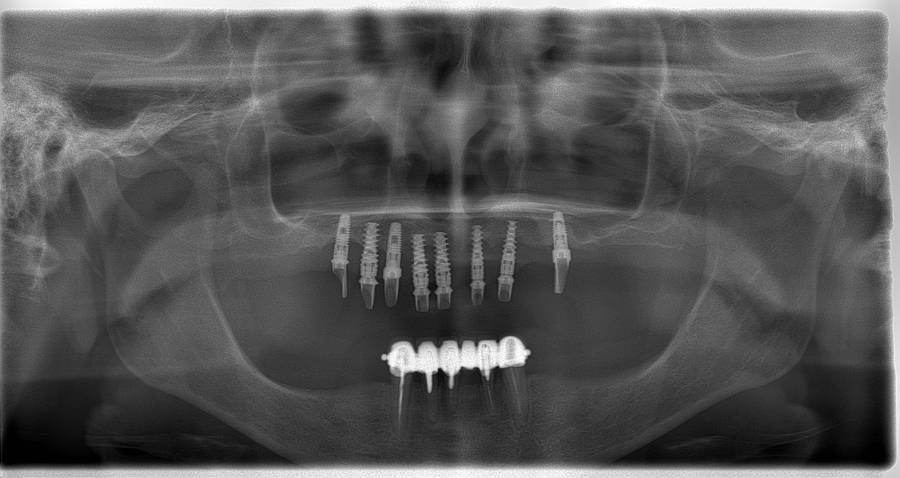

Исследование на рентгене после имплантации зубов

Раздел: Снимки-откровения